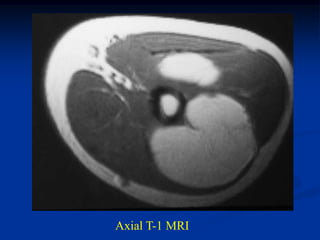

CLASSIC       Case #279      Sagittal T-1 MRI

63 year female with myxolipoma knee